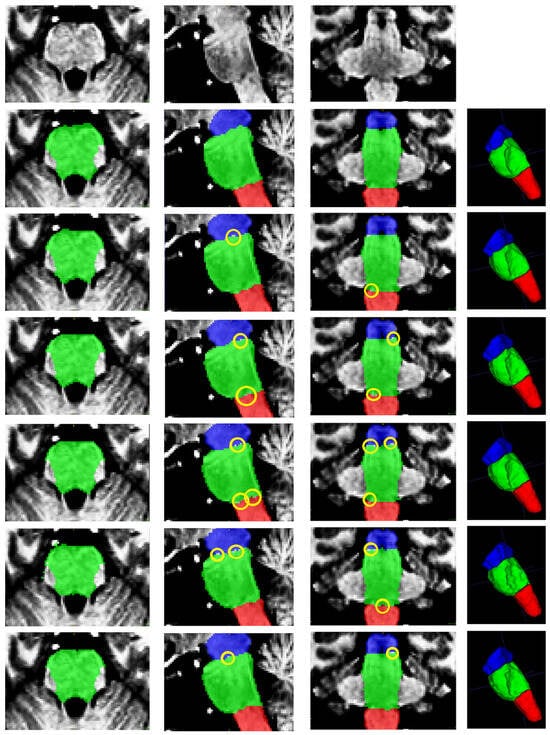

- Superior Segmentation Performance: The proposed modified U-Net architecture (with attention-enhanced skip connections and inception modules) significantly outperforms three comparative approaches in brainstem parcellation, achieving higher scores across all substructures (medulla, pons, and mesencephalon) and the whole brainstem.

- Volume Differences Across Groups: Automated segmentation reveals distinct volumetric patterns, with controls exhibiting larger volumes (whole brainstem: 1.62) compared to preclinical (1.49) and patient groups (1.12), suggesting potential atrophy linked to disease progression.

- Clinical Utility: The method’s accuracy and robustness support its potential for precise brainstem assessment in neurodegenerative disorders, enabling earlier detection of structural changes (e.g., reduced medulla volume in patients: 0.26 vs. 0.31 in controls).